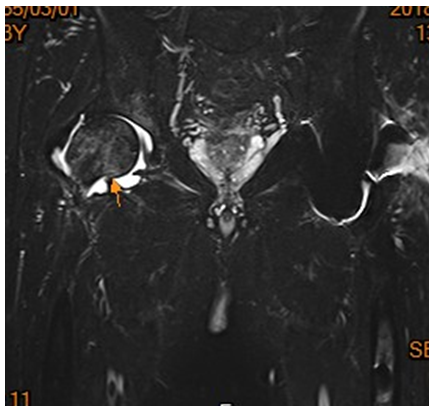

患者的主要症狀以患肢負重疼痛為主,意思就是走路會痛,疼痛的部位在鼠蹊部或是髖部深處,有時膝蓋也會有牽引痛。理學檢查可以發現髖部活動受限或是轉動檢查(Patrick test)會痛。如果骨頭結構已經被破壞及吸收了,是可透過X光檢查清楚發現的(圖一);若需要早期發現,則必須仰賴核磁共振(MRI)檢查(圖二)。

(圖二)